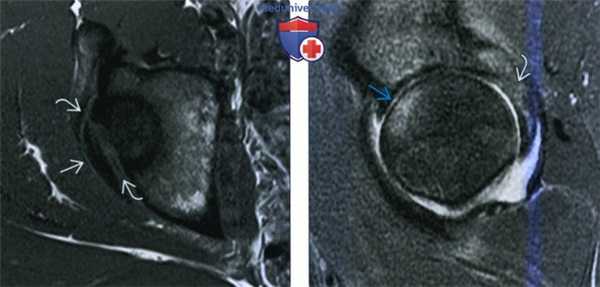

4. МРТ при вывихе бедра:

• МРТ не показано пациентам с острой травмой:

о Используется для постановки диагноза посттравматического остеонекроза

• Травма атлетов при вывихе обычна транзиторная, а картина визуализации при рентгенографии нормальная:

о МРТ выполняется для оценки причин боли в бедре, могут быть выявлены:

- Разрыв задней губы, травма капсулы

- Перелом задней стенки/губы вертлужной впадины

- Ушиб кости (отек): головка бедренной кости спереди и кзади от вертлужной впадины

- Повреждение хряща

- Повреждение круглой связки

о В таких случаях следует заподозрить стрессовый перелом головки бедренной кости, помимо травмы мышцы/сухожилия:

- Для визуализации других травм необходимо включить коронарный срез таза с полным полем зрения

(Слева) МРТ Т1, аксиальный срез: у футболиста с болью после получения травмы, определяется гипоинтенсивный полулунный осколок задней стенки вертлужной впадины. Осколок перелома немного смещен.

(Справа) MPT, STIR, сагиттальный срез: у этого же пациента определяется выпот в полость сустава, отек головки бедренной кости спереди. Эти признаки указывают на ушиб с повреждением вышележащего хряща, а также на отек в месте перелома задней вертлужной впадины. Данные признаки служат критерием транзиторного заднего вывиха.